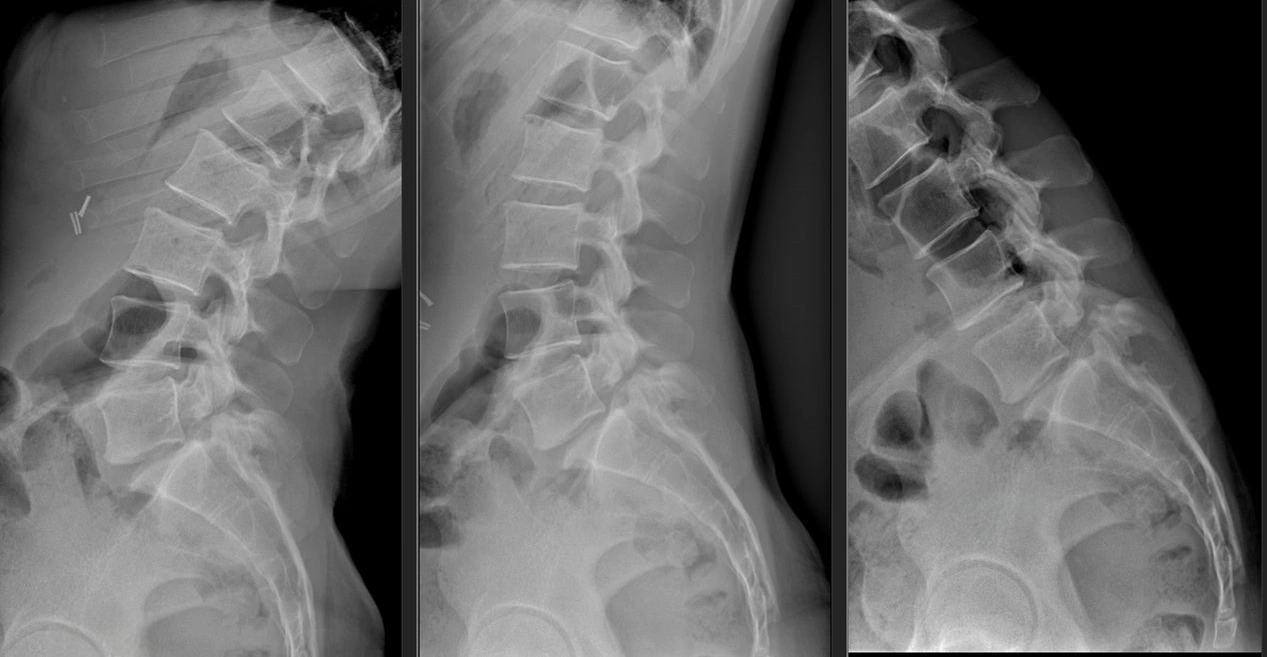

Trattamento chirurgico della spondilolistesi e della stenosi lombare

La spondilolistesi (scivolamento di una vertebra sull’altra) e la stenosi del canale lombare (restringimento dello spazio in cui scorrono le strutture nervose) possono causare lombalgia, sciatalgia, difficoltà alla marcia e, nei casi avanzati, deficit neurologici.

Quando la sintomatologia è importante e non risponde alle cure conservative, l’obiettivo della chirurgia è duplice: decomprimere le strutture nervose e ristabilire la stabilità del segmento vertebrale.

A Villa dei Fiori si utilizzano sia approcci posteriori tradizionali sia tecniche mini-invasive di ultima generazione. Tra queste rientrano gli interventi di artrodesi lombare con accesso transmuscolare (secondo i principi dell’accesso di Wiltse) e l’artrodesi intersomatica obliqua transforaminale (OLIF), che consentono di:

• creare uno spazio di lavoro attraverso i muscoli, senza doverli scollare dall’osso;

• decomprimere il canale vertebrale rimuovendo solo ciò che è strettamente necessario;

• inserire cage tra i corpi vertebrali e sistemi di viti e barre che stabilizzano il segmento;

• ridurre il trauma chirurgico, il sanguinamento e il dolore post-operatorio.

Il risultato è una chirurgia più rispettosa delle strutture anatomiche, con una degenza più breve, una mobilizzazione molto precoce e un recupero funzionale più rapido, pur garantendo una solida fusione vertebrale e una adeguata decompressione delle radici nervose.